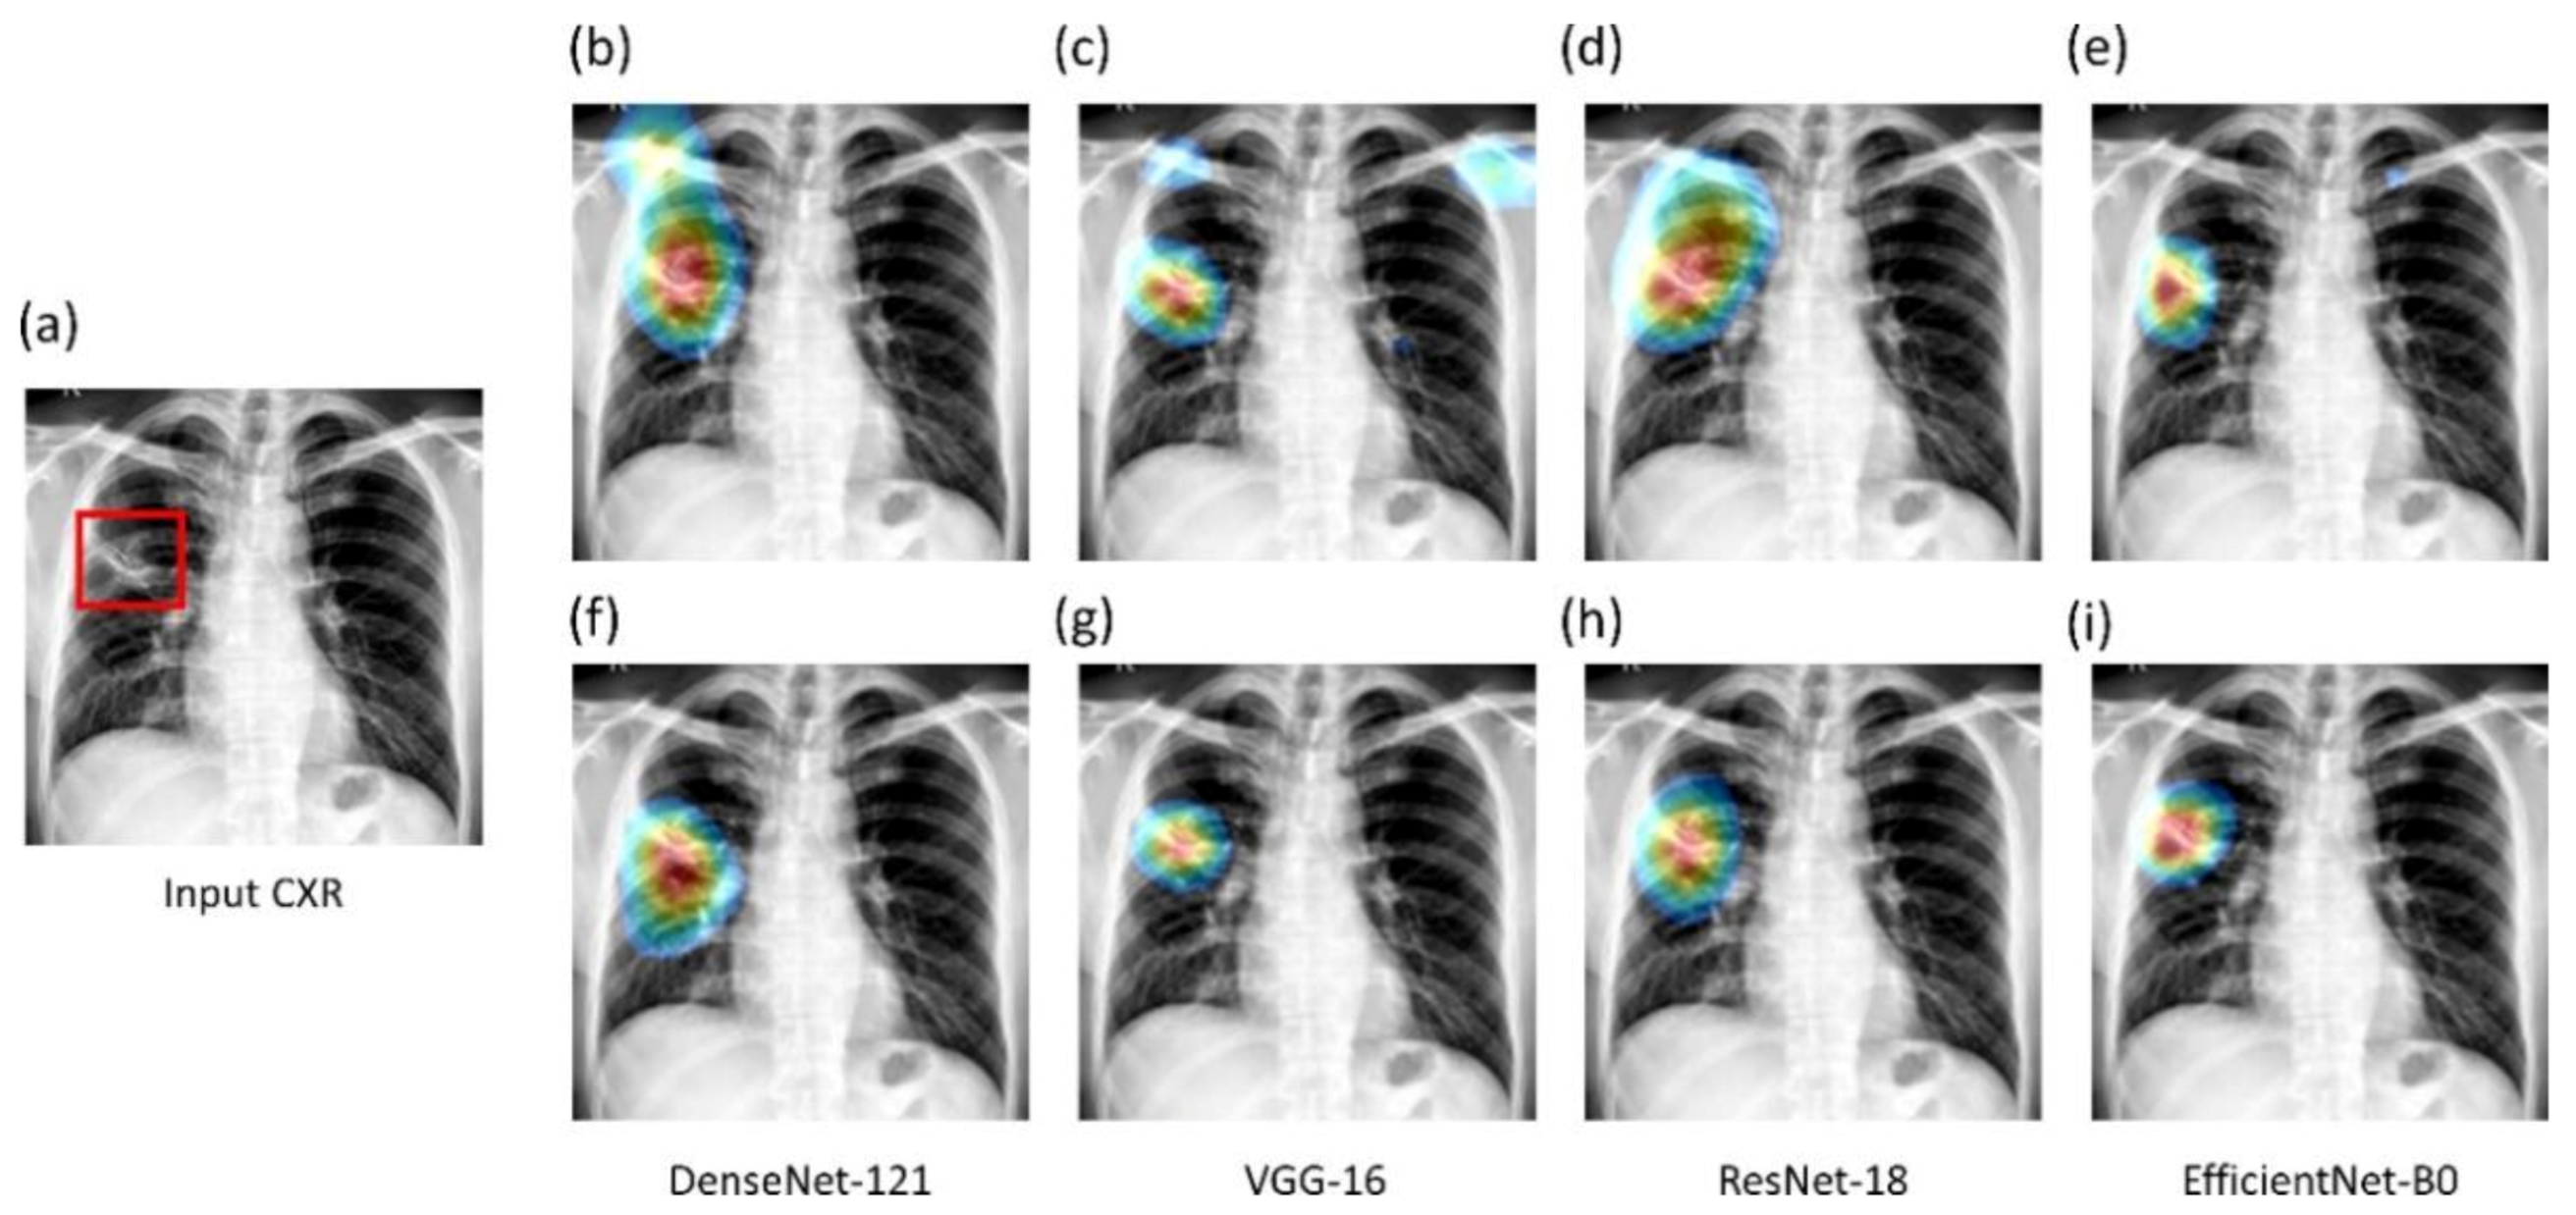

We used saliency maps and a CRM-based localization algorithm [

34] to interpret the learned behavior of the fine-tuned models toward detecting TB manifestations. These algorithms provide a visual interpretation of model predictions and supplement clinical decision-making. The algorithms differ by the methods in backpropagating the derivatives and the use of feature maps. Saliency maps measure the derivative of the output category score concerning the original input and generate a heat-map with the original input image resolution. A higher derivative value signifies the importance of that activation in contributing to the final category score. A smaller value for the derivative results in negligible impact, and the activation can thus be considered trivial toward final prediction.

CRM-based visualization algorithms are demonstrated to deliver superior localization performance as compared to the conventional class-activation map (CAM)-based localization, particularly toward medical image analysis [

34]. Unlike CAM-based visualization, CRM-based localization underscores the fact that the feature maps contribute to decreasing the prediction scores for other class categories in addition to increasing the scores for the expected category. Such discrimination helps in maximizing the difference between these scores and results in superior discrimination of class-specific ROI by measuring the incremental mean-squared error from the output nodes. The features are extracted from the deepest convolutional layer of the best-performing fine-tuned model. The CRM algorithm is used to localize the ROI involved in classifying the CXRs as showing pulmonary TB manifestations. The feature map dimensions vary across the models. Hence, the CRMs are upscaled through normalization methods to match the spatial resolution of the input image. The computed CRMs are overlaid on the original image to localize the TB-consistent ROI that is used to categorize the CXRs as showing pulmonary TB manifestations. The CRMs are generated for the CXRs with TB-category labels toward visualizing the regions of TB manifestations. We further converted these CRM-based weak TB-consistent ROI localizations to binary ROI masks. The original CXRs and the associated ROI masks are used for further analysis.

Verifying ROI localization: neural networks make use of inherent learning methods to identify salient features in the input data. However, data-driven DL models are considered back-boxes since they lack explainability. Therefore, it is crucial to determine if these models are predicting the expected classes for the right reasons. Saliency maps and other visual ablation studies help to investigate if the models learn salient feature representations conforming to the experts’ knowledge of the problem. In this study, we used saliency maps and CRM-based localization algorithms to illustrate and explain the localization behavior of the trained models. We observed that the TB-consistent ROI localization obtained with the CXR modality-specific fine-tuned models are superior to those obtained using the ImageNet-pretrained models. Such superior localization performance could be attributed to the following characteristics: (i) the fine-tuned models inherit CXR modality-specific knowledge compared to that transferred from the natural image domain; (ii) the transferred knowledge is relevant to the target modality; (iii) the fine-tuned models are empirically truncated at the optimal depth to learn relevant and salient feature representations. This helped to deliver superior classification and localization performance. These observations are reinforced by the suboptimal localization performance observed with the out-of-the-box ImageNet-pretrained models.